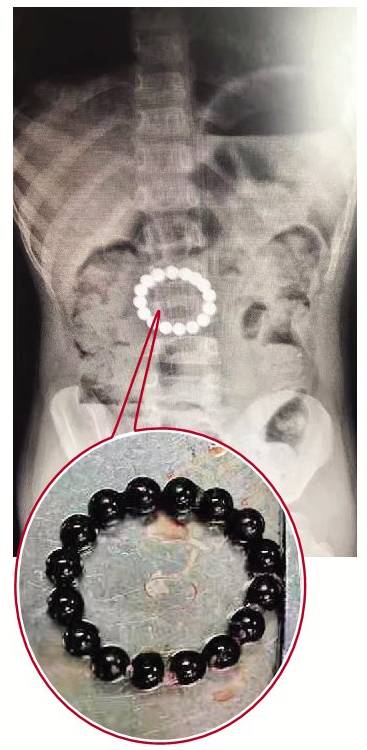

溫州4歲女童誤吞16顆磁鐵,在體內(nèi)“串”成一串手鏈,引起腸穿孔。

女孩因為腹痛嘔吐兩天,家人把她送到醫(yī)院急診科。X光檢查讓醫(yī)生大吃一驚:女孩的腸子里有一串手鏈狀的異物!笆宙湣庇墒畮最w珠子組成,緊緊地挨在一起。經(jīng)過詢問,女孩家長告訴醫(yī)生,家里有一種叫巴克球的玩具,由上百顆磁力珠組成,看上去很像巧克力豆。

圖為女童X光片下的“手鏈”

圖為從女童腹中取出的16顆磁鐵